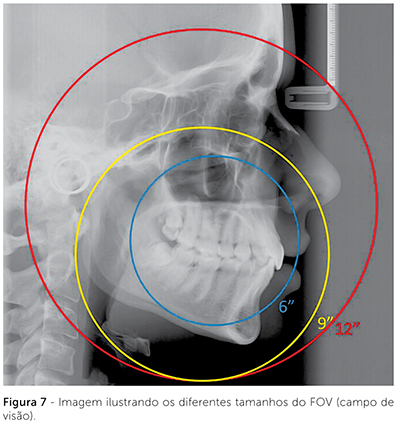

O campo de visão, ou FOV (Field of View), dos aparelhos cone beam, normalmente trabalha com janelas entre 6″ e 12″. O FOV de 6″ é utilizado quando se quer imagens restritas a apenas um dos maxilares. No FOV de 9″ é possível visualizar ambos os maxilares e, dependendo do tamanho do paciente, todo o complexo craniofacial. Entretanto, quando se quer que toda a região craniofacial esteja inserida no estudo, como nos casos onde se quer analisar cefalometricamente o paciente, deve-se selecionar o FOV de 12″ (Fig. 7)7,3,16,18.

As estruturas e pontos de referência usados nas análises ortodônticas incluem a base do crânio, os ossos da face e a dentição, o que requer um campo de visão maior do que o usado nas análises para implantes. De forma geral, o ortodontista necessita visualizar o násio, no limite anterossuperior da imagem; e os pontos mandibulares pogônio, gnátio e mento, no limite anteroinferior. O campo de visão posterior deve incluir a sela túrcica, as ATMs (ponto condílio), a base do crânio (básio), e o contorno posterior da mandíbula (gônio). Além disso, as vértebras, até a C4, devem estar visíveis na tomografia, permitindo a análise da maturação esquelética21.